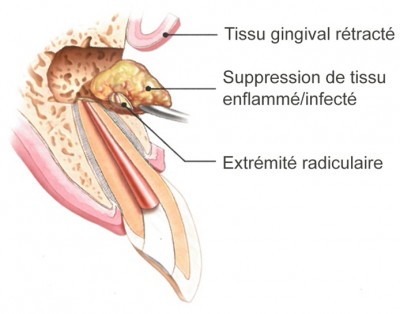

Chirurgie endodontique

La chirurgie endodontique est une intervention chirurgicale de l'apex dentaire en présence de kyste péri radiculaire.

Elle consiste à la résection de la partie apicale de la racine dentaire et à procéder au curetage du tissu pathologique périapical. Elle comprend une obturation hermétique de la racine au niveau du système canalaire apical.

La chirurgie endodontique est une technique codifiée et reproductible offrant une solution fiable pour conserver l'organe dentaire.

Elle fait partie intégrante de l'arsenal thérapeutique, et permet de résoudre des situations pour lesquelles les traitements endodontiques ont leurs limites.

Elle consiste à la résection de la partie apicale de la racine dentaire et à procéder au curetage du tissu pathologique périapical. Elle comprend une obturation hermétique de la racine au niveau du système canalaire apical.

La chirurgie endodontique est une technique codifiée et reproductible offrant une solution fiable pour conserver l'organe dentaire.

Elle fait partie intégrante de l'arsenal thérapeutique, et permet de résoudre des situations pour lesquelles les traitements endodontiques ont leurs limites.